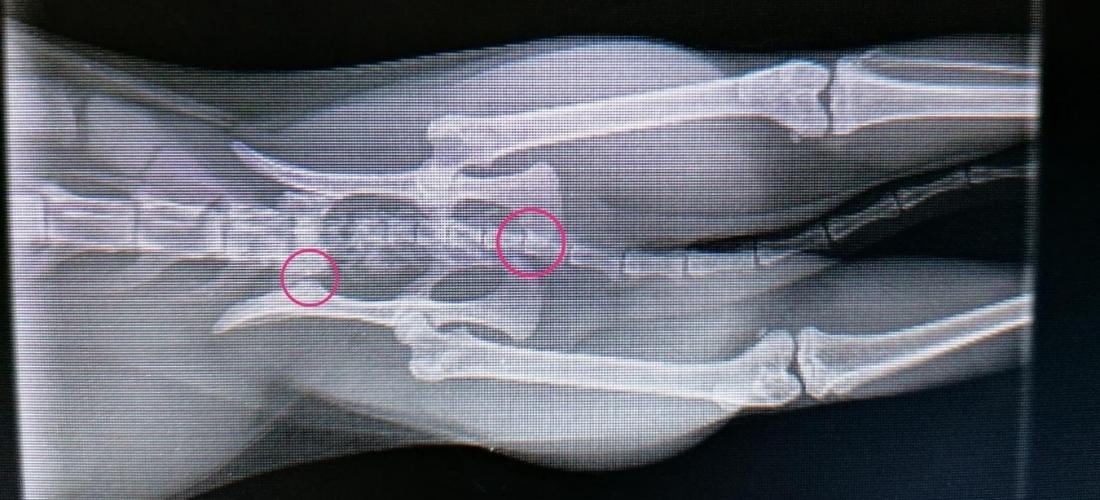

PDSA Vet, Jo Milne, said: “When Rosie came to the Pet Hospital, she was seriously injured and struggling to use her hind legs despite receiving strong pain relief. We carried out X-rays under anaesthetic, which sadly confirmed she had a fractured pelvis but had luckily escaped any internal injuries.”

PDSA Vet, Jo Milne, continued: “Complex pelvic fractures often require a surgical repair with a vet who specialises in such cases, but some will heal given enough time and strict rest. In Rosie’s case, her owner couldn’t afford a costly referral so the next 48 hours were crucial. We needed to ensure Rosie’s injuries would heal without an operation and that she did not have serious nerve damage that could cause her long-term problems.”